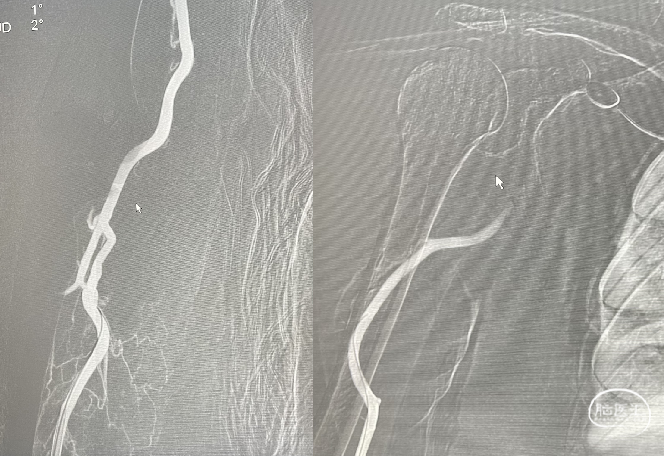

2、通路的建立:患者左侧椎动脉起始部异常迂曲,无法建立稳定的通路;而右侧的椎动脉走向相对较好,但是右侧锁骨下动脉向下,向后走,从传统的股动脉入路也是难以建立稳定的通路,而通过右桡动脉可以建立稳定的通路。

建立通路:经桡动脉入路,取腕关节桡动脉搏动点穿刺,右侧桡动脉成功,置入6F鞘,顺导管鞘送入260mm泥鳅导丝,并利用260mm交换导丝将6F长鞘交换至右侧锁骨下动脉,U-Track™ 5F中间导管在微导丝+PLUS微导管的导引下顺利到达基底动脉动脉瘤附近。